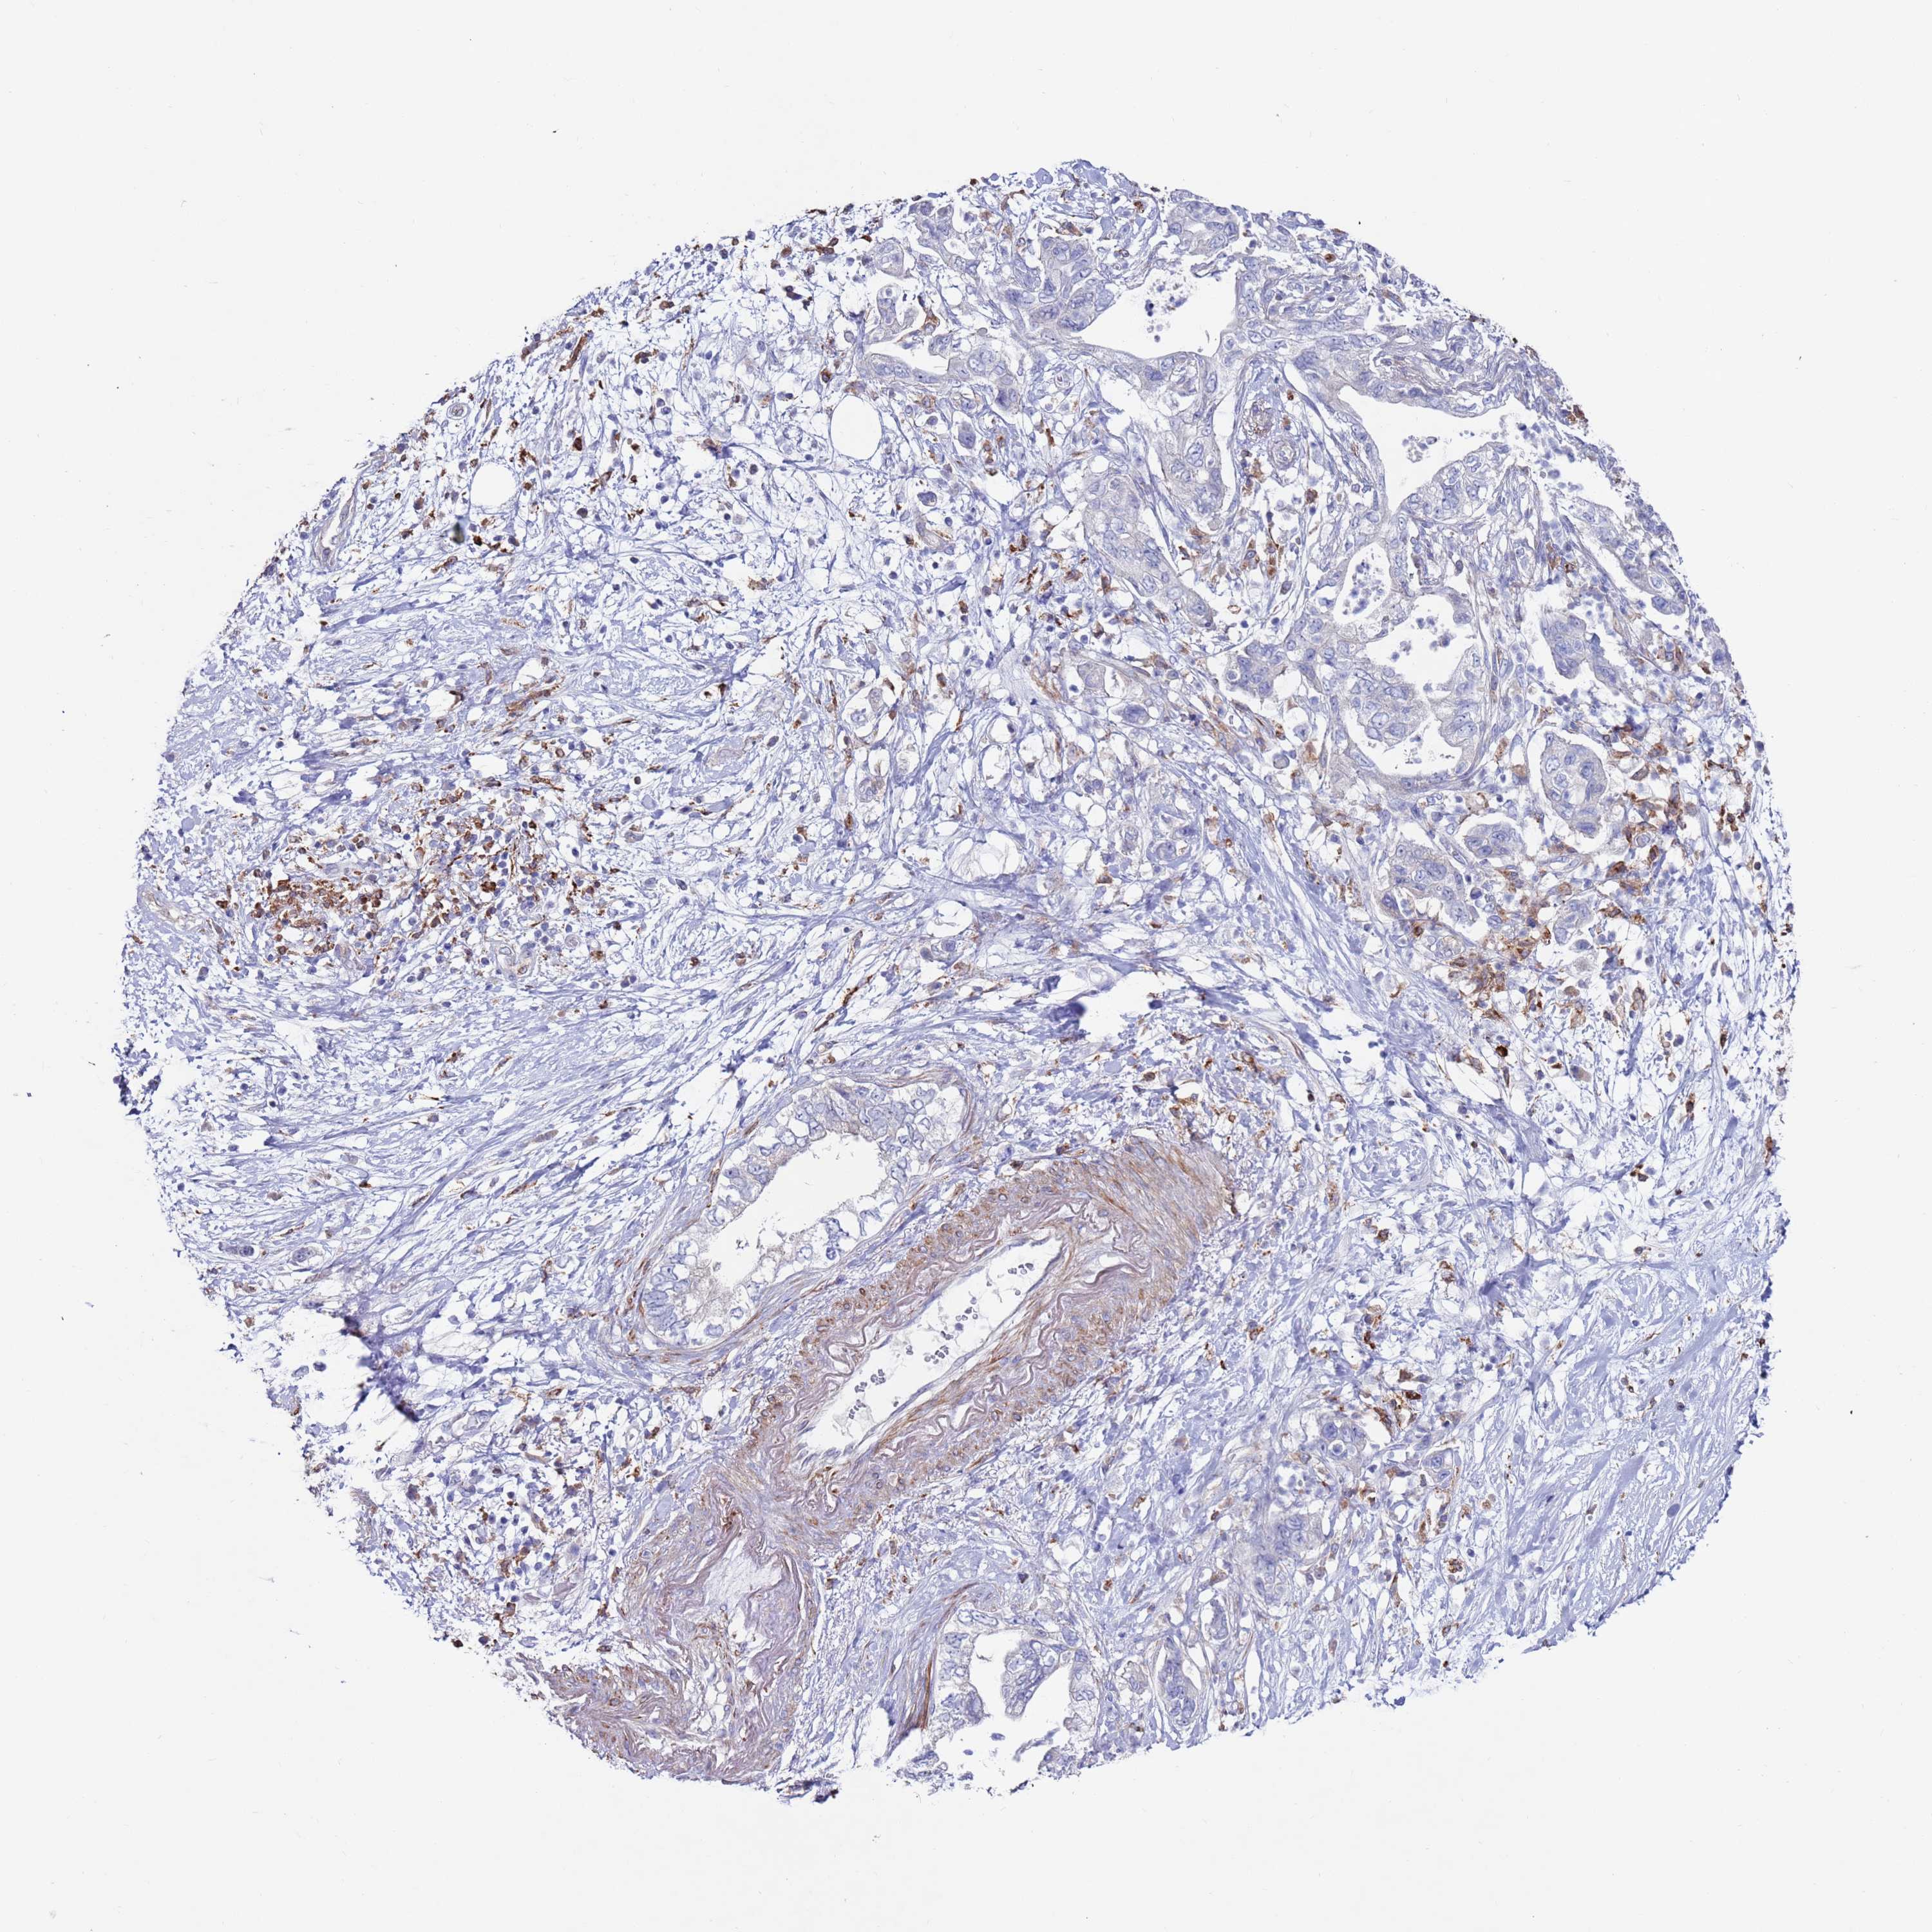

PANCREATIC CANCER - Protein expressioni

A mouse-over function shows sample information and annotation data. Click on an image to view it in a full screen mode. Samples can be filtered based on level of antibody staining by selecting one or several of the following categories: high, medium, low and not detected. The assay and annotation is described here.

Note that samples used for immunohistochemistry by the Human Protein Atlas do not correspond to samples in the TCGA dataset.

Antibody stainingi

Antibody staining in the annotated cell types in the current human tissue is reported as not detected, low, medium, or high, based on conventional immunohistochemistry profiling in selected tissues. This score is based on the combination of the staining intensity and fraction of stained cells.

Each image is clickable and will lead to virtual microscopy that enables deeper exploration of all samples and also displays staining intensity scores, fraction scores and subcellular localization as well as patient and tissue information for each sample.

Antibody HPA041647

Antibody HPA044218

Adenocarcinoma, NOS